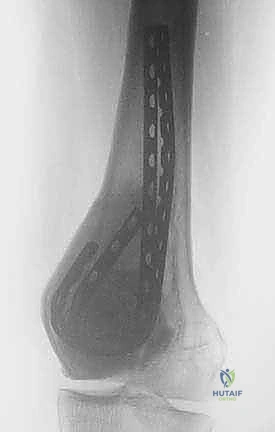

Complementing the MRI, high-resolution computed tomography (CT) is invaluable for assessing the integrity of the cortical shell and the subchondral bone plate. CT provides the best architectural map for planning the cortical window and assessing the risk of postoperative fracture. Baseline plain radiographs in orthogonal planes remain crucial for initial assessment, overall bone morphometry, and long-term postoperative comparison.

Example: Radiographic evaluation of a giant cell tumor of the proximal tibia, highlighting the subchondral involvement and the necessity for joint-preserving techniques.

Intraoperative fluoroscopy and clinical images confirming the placement of robust internal fixation spanning the reconstructed defect.

Final radiographic verification of the reconstruction, demonstrating excellent alignment, hardware placement, and complete filling of the defect.